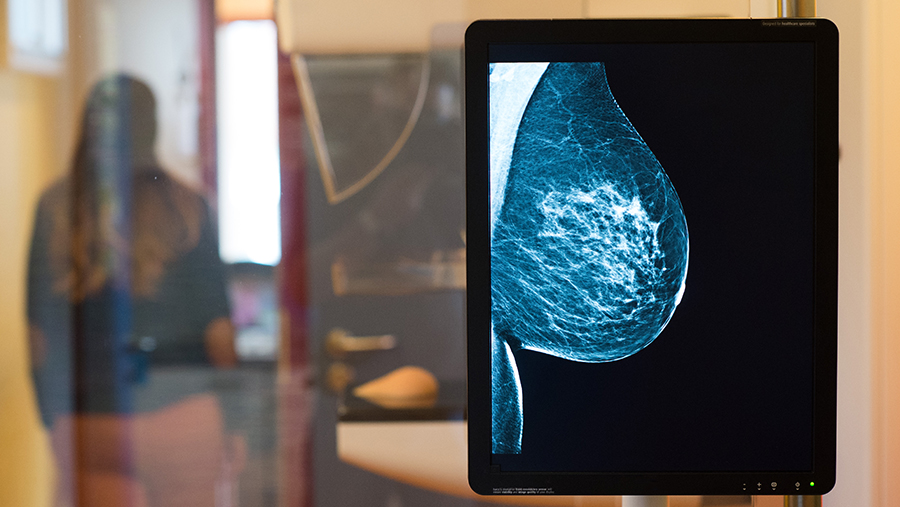

Рак молочной железы остается самым распространенным онкологическим заболеванием среди женщин, однако раннее выявление значительно повышает шансы на успешное лечение: до 98% пациенток полностью выздоравливают при диагностике на первой стадии. Об этом 8 декабря заявила «Известиям» врач-онколог, маммолог Елена Жукова.

«Ранние признаки и симптомы рака груди у женщин не всегда проявляются сразу, а визуальные изменения пациентки замечают уже с ростом опухоли. Тем не менее самодиагностика важна для регулярного контроля здоровья. Лучше всего ее проводить на 5–12-й день менструального цикла. Молочные железы стоит не только осмотреть, но и проверить на ощупь», — пояснила специалист.

Эксперт сообщила, что необходимо насторожиться при появлении уплотнения в молочной железе, особенно если оно не связано с циклом и остается малоподвижным. Опасным сигналом может стать внезапная асимметрия, когда одна грудь увеличивается или уменьшается без видимых причин. Еще один тревожный признак — отек кожи, который создает эффект «апельсиновой корки» из-за поражения лимфатических сосудов.

Особое внимание, по словам врача, следует уделять изменениям соска и ареолы: втяжение, изменение формы или появление незаживающих участков на коже требуют консультации специалиста. Подозрение вызывает и появление выделений, особенно односторонних и с примесью крови. Увеличенные подмышечные лимфоузлы, плотные и малоподвижные, могут говорить о распространении опухолевого процесса раньше, чем проявится сам очаг.

Даже чувство распирания или покалывания в груди иногда сопровождает редкие воспалительные формы рака, при которых железа становится горячей, краснеет и болит. Однако Жукова подчеркнула, что на ранних стадиях заболевание зачастую протекает без симптомов, поэтому ежегодную диспансеризацию — УЗИ и маммографию — необходимо проходить каждой женщине, а осмотр маммолога должен стать регулярным.

«Если вы обнаружили у себя один или несколько признаков онкологии, это не повод паниковать. Очень часто с онкологией путают другие образования: кисты, мастопатии, маститы и папилломы. Первый шаг — обратиться к специалисту для проведения более точной диагностики», — заключила специалист.